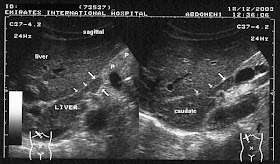

However, images 3 and 4, reveal a different diagnosis- the possible "mass" appears to be an extension of the caudate lobe of the liver. These ultrasound images are diagnostic of "papillary process of the caudate lobe of liver."This normal variant may thus mimic pancreatic or preaortic lymph node masses.

3-

4-